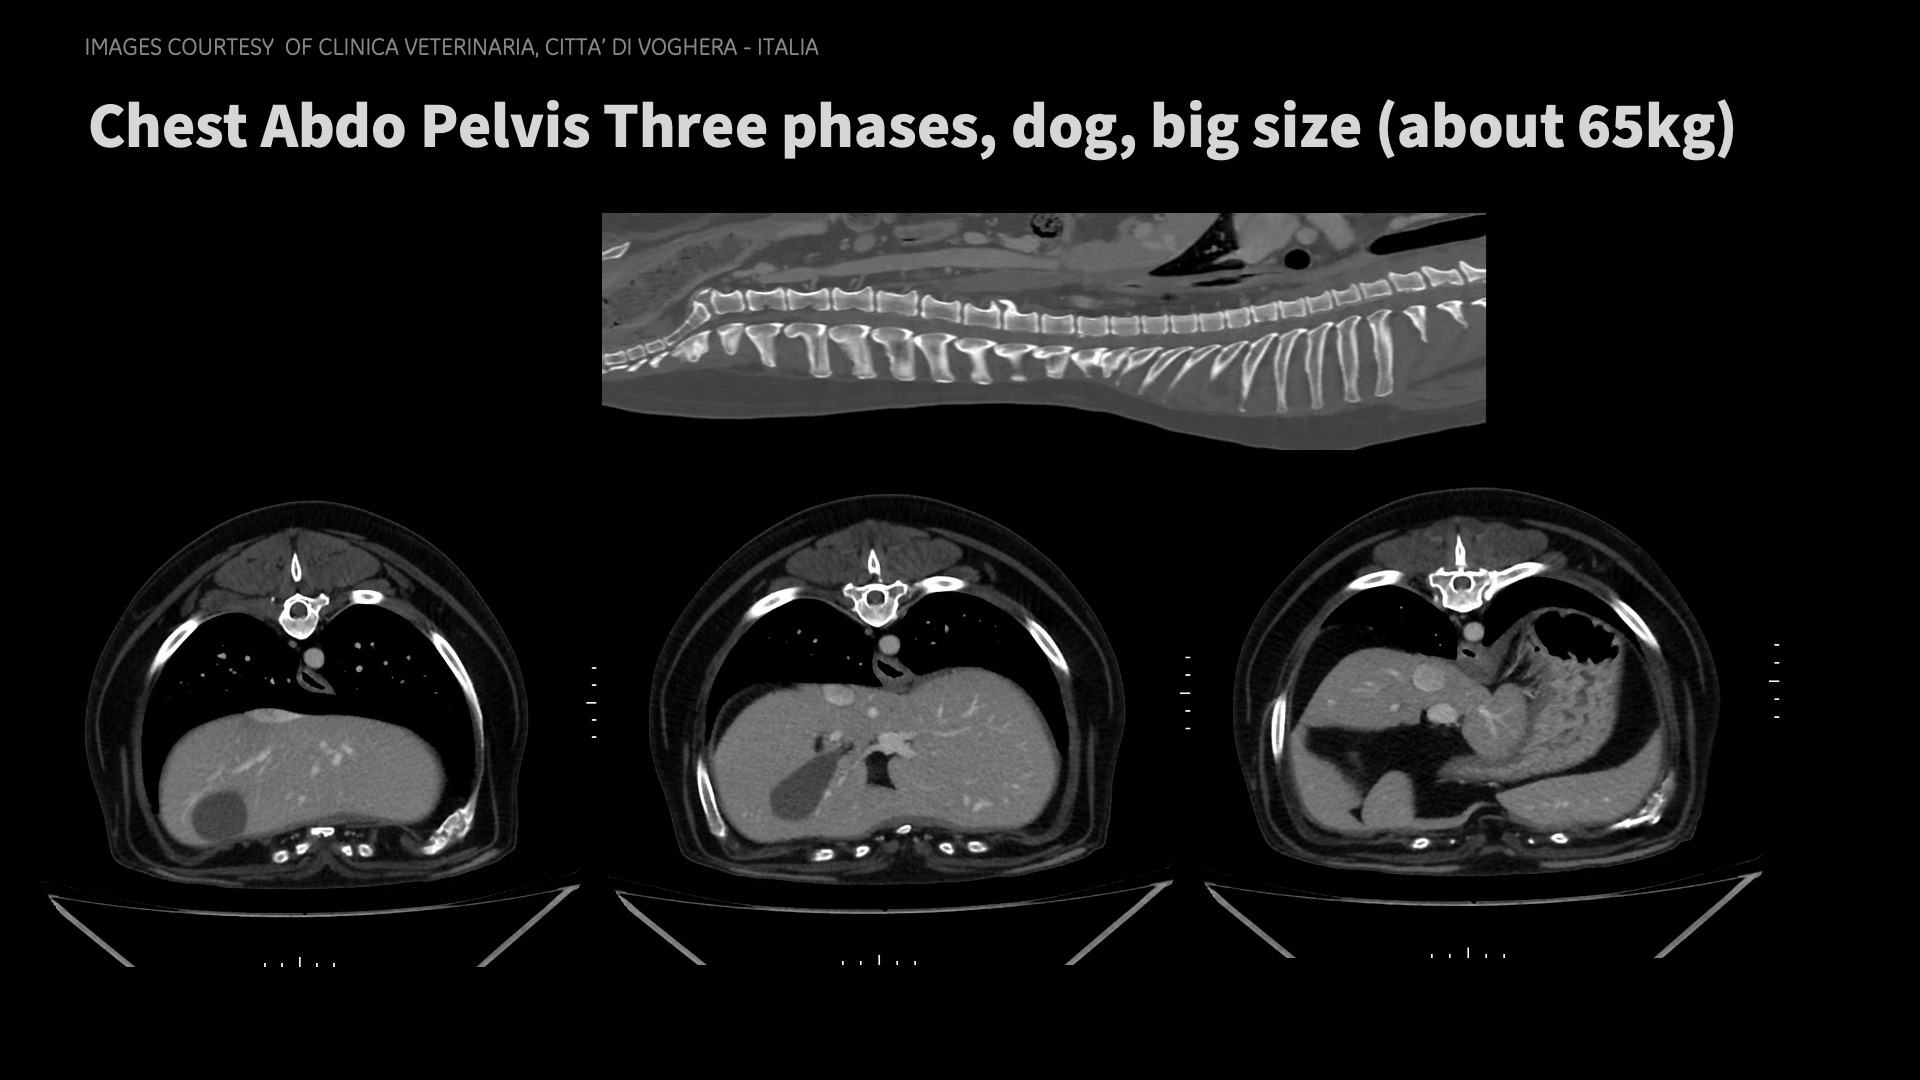

Clinical images

Don’t need to be an eagle to see the details